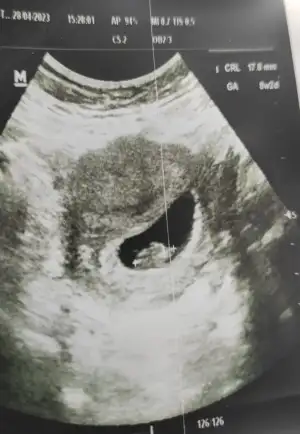

Biz keseyi 5+6’da gördük

Kalp atışını ise 6+1’de ama bebek 6+2 çıktı